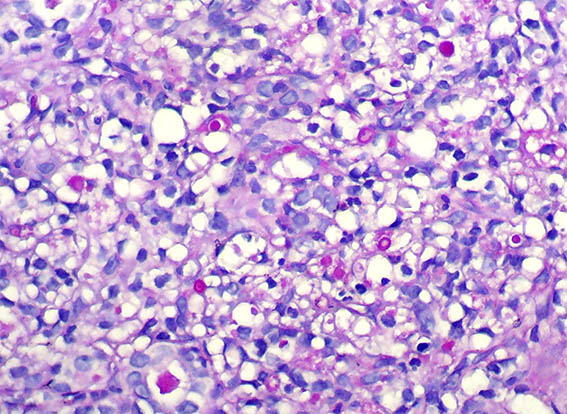

Figure 5. H&E, X400.